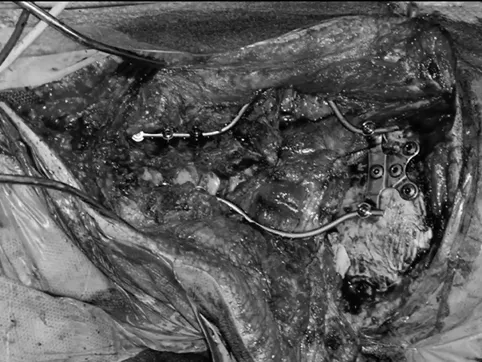

手术记录:福教授考虑肿瘤已经导致颅颈交界区骨质结构的广泛损害和侵蚀,术前评估手术后会出现颅颈不稳定。因此,经远外侧经髁入路进行显微镜+神经内镜双镜联合切除肿瘤,然后枕颈融合术(OCF)。

▼使用神经内镜辅助探查肿瘤,备行内镜手术

▼“筷子技术”神经内镜切除对侧肿瘤

▼使用自体脂肪填充瘤腔及关颅

▼使用PMMA材料枕髁重建

使用Roy-Camille技术进行枕颈融合术(C0-C3-C4-C5),固定根钉以曲线方式横向弯曲,为后续质子治疗创造一个无金属的定位及治疗通道。术后CT和MRI显示肿瘤完全切除。病理证实为典型脊索瘤。在术后恢复中,患者吞咽功能好转和颈部疼痛缓解。8周后,他接受了质子治疗。

▼将根钉弯曲以便于后续质子治疗